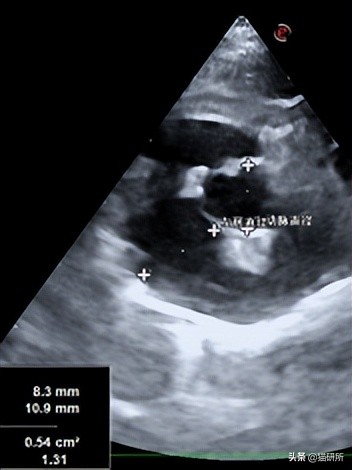

TMT和HCM小猫的重要指标 感兴趣可以点开大图看 图自:引文[1]

HCM患猫

在没有异常负荷情况下, 左室壁厚度仍会>6mm ;

TMT患猫

是发病初始左室壁最大厚度>6mm, 病情后期症状改善会下降到<5.5mm ;